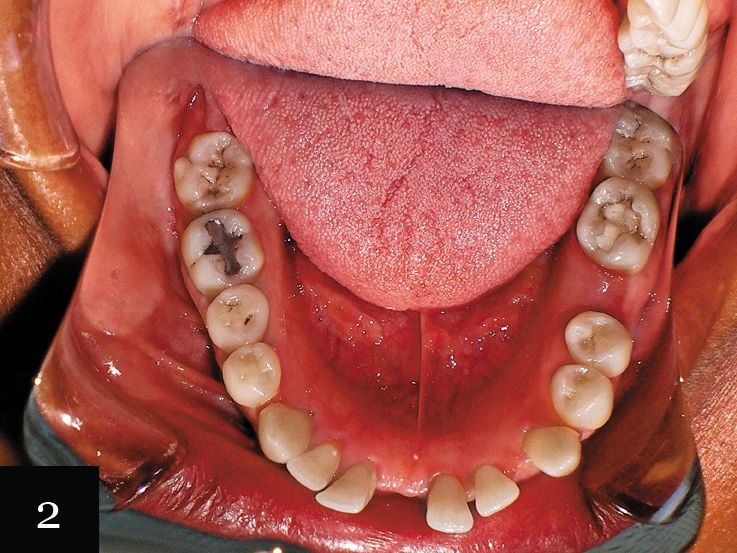

Case No. 1

This patient was a 55-year-old woman with a large space in her lower arch (Fig. 1). Despite this space, the patient was not missing any teeth. Figure 2 shows the impression-taking challenge-capturing the distal edge of the molars while also capturing the forward angle of the front teeth.

The impression was successfully captured on the first try, and the patient was treated with a series of 32 aligners over 16 months. The final result shows the closed space in the mandible and the dramatic esthetic improvement (Figs. 3 and 4).